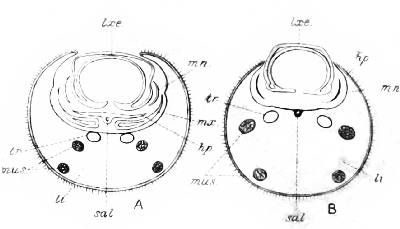

Fig. 13—Pathogenic Protozoa; a group of intestinal

parasites. A, B, Megastoma entericum, C, Balantidum entozoon.

(After Calkins.)

Fig. 13—Pathogenic Protozoa; a group of intestinal

parasites. A, B, Megastoma entericum, C, Balantidum entozoon.

(After Calkins.)